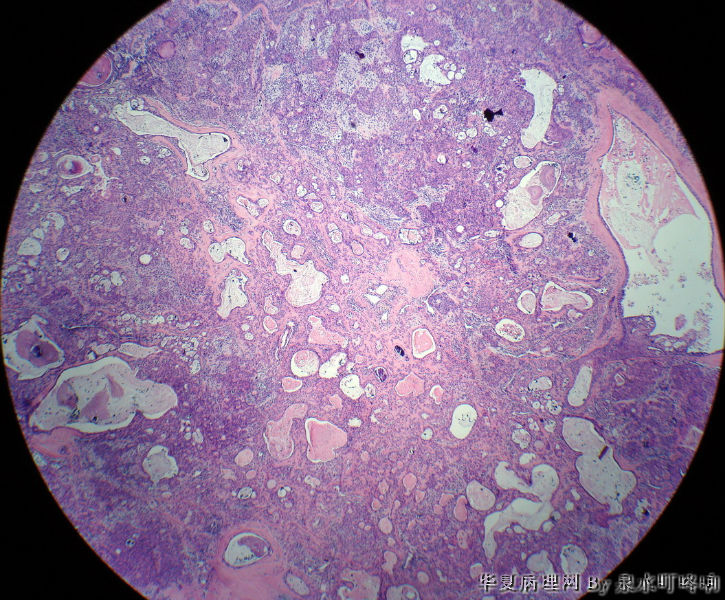

左腮腺肿物

女,38岁,左耳下方肿物,临床诊断:左腮腺肿物。

大体:灰白肿物一个,大小约4×3.5×3厘米,切面灰白,质略软,可见多发囊腔。

(左腮腺)多形性腺瘤

多形性腺瘤(粘液软骨样区域+上皮成分)

瘤组织由多种上皮成分(腺上皮+肌上皮+鳞化上皮)及黏液软骨样基质构成,多形性腺瘤可以囊性变,多结节状分布。

多形性腺瘤,肌上皮、腺上皮增生,鳞化、粘液背景

1、境界清楚

2、两种类型细胞:导管上皮+肌上皮,肌上皮与周围间质有融合现象。

3、伴有角化的鳞状分化。

4、间质:软骨粘液样间质+弹力纤维。

综上:多形性腺瘤。